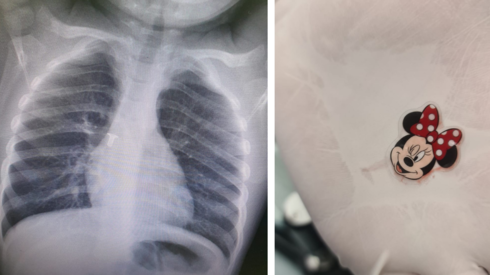

"בשל סכנת החיים המיידית בה נמצאה אשר בה כל דקה משמעותית, הוחלט על הרדמת התינוקת. ד"ר אביב טוטנאור, מומחה בהרדמה וברפואת כאב במרכז שניידר: "בשלב הזה הילדה כבר הכחילה. החלטנו מידית לבצע אינטובציה. הנשמתי אותה במנשם ידני (מפוח הנשמה) ומסכה. כאשר הורדמה, בעזרת לרינגוסקופ, בצעתי פתיחה של פיה לצורך הסתכלות על דרכי האוויר. שם ציפתה לי הפתעה, מדבקת מיני מאוס חייכה אליי".

לפיה של התינוקת הוחדר וקובע צינור פלסטי (טובוס) אל תוך קנה הנשימה בין מיתרי הקול וד"ר טוטנאור שלף מגופה מדבקת פלסטיק קטנה בצורת מיני מאוס. לאחר שליפת המדבקה, הועברה התינוקת לחדר הניתוח לבדיקת ברונכוסקופיה, בדיקה הבוחנת באמצעות מצלמת וידאו זעירה את קנה הנשימה ולא נמצאו גופים זרים נוספים. התינוקת הועברה להשגחה ביחידה לטיפול נמרץ בראשותו של פרופ' אלחנן נחום ובהמשך שוחררה לביתה.